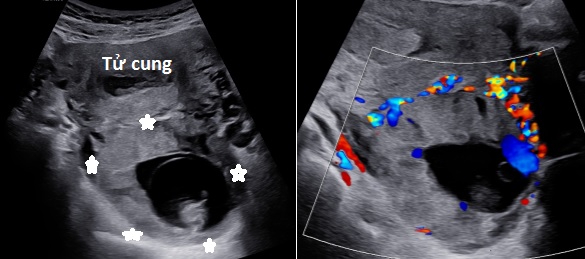

Hình 1: Siêu âm ngã bụng cho thấy khối thai nằm ở mặt sau tử cung, ở cùng đồ sau, lòng tử cung có lớp dịch, trên Doppler màu có hình ảnh tăng sinh mạch máu nhiều quanh khối thai.

Hình 2: Siêu âm ngã âm đạo cho thấy khối thai nằm sau tử cung, bánh nhau ăn chặt vào cơ tử cung thành sau (hình sao), không có lớp cơ bao quanh khối thai.

Siêu âm với máy HERAW9 Samsung ngã bụng kết hợp với âm đạo cho thấy: Tử cung to, đường kính trước sau 70 mm, lòng tử cung ứ dịch. Hai buồng trứng bình thường. Phía sau tử cung có khối thai, bên trong có phôi thai sống với chiều dài phôi thai 40 mm, không quan sát thấy lớp cơ tử cung bao quanh túi thai, không thấy dãi mô liên tục giữa khối thai và tử cung. Trên Doppler màu có hình ảnh tăng sinh mạch máu quanh túi thai, ở vị trí sau nhau rất nhiều.

Hình ảnh siêu âm của chúng tôi là một khối được xác định là thai (túi thai có yolksac, màng ối, bánh nhau, phôi thai có tim thai) nằm ở cùng đồ sau và không có lớp cơ bao quanh túi thai. Điều này hướng chúng tôi nghĩ đến chẩn đoán thai trong ổ bụng.